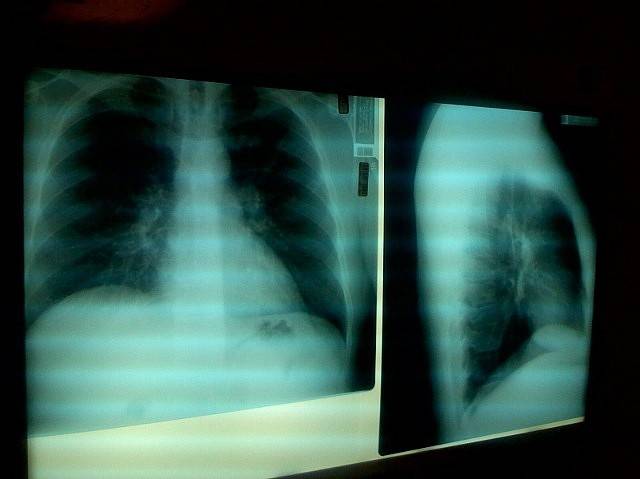

La neumonía es una complicación grave pero relativamente frecuente entre las personas con enfermedad de Alzheimer, y a menudo conduce a la hospitalización e incluso a la muerte. Los opiáceos son importantes en el tratamiento del dolor agudo severo, pero el tratamiento debe iniciarse en dosis bajas y evaluarse regularmente tanto en términos de beneficios como de daños.